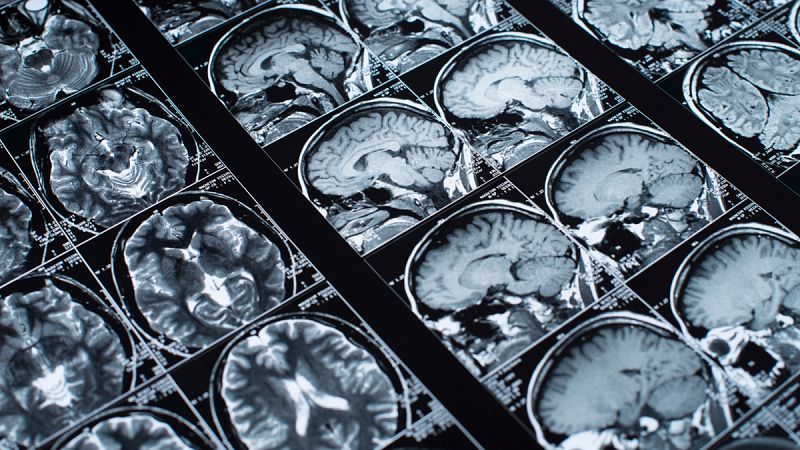

Neurocientíficos franceses han descubierto que hay regiones que solo se activan en los cerebros de matemáticos expertos, en contraste con los no especialistas.